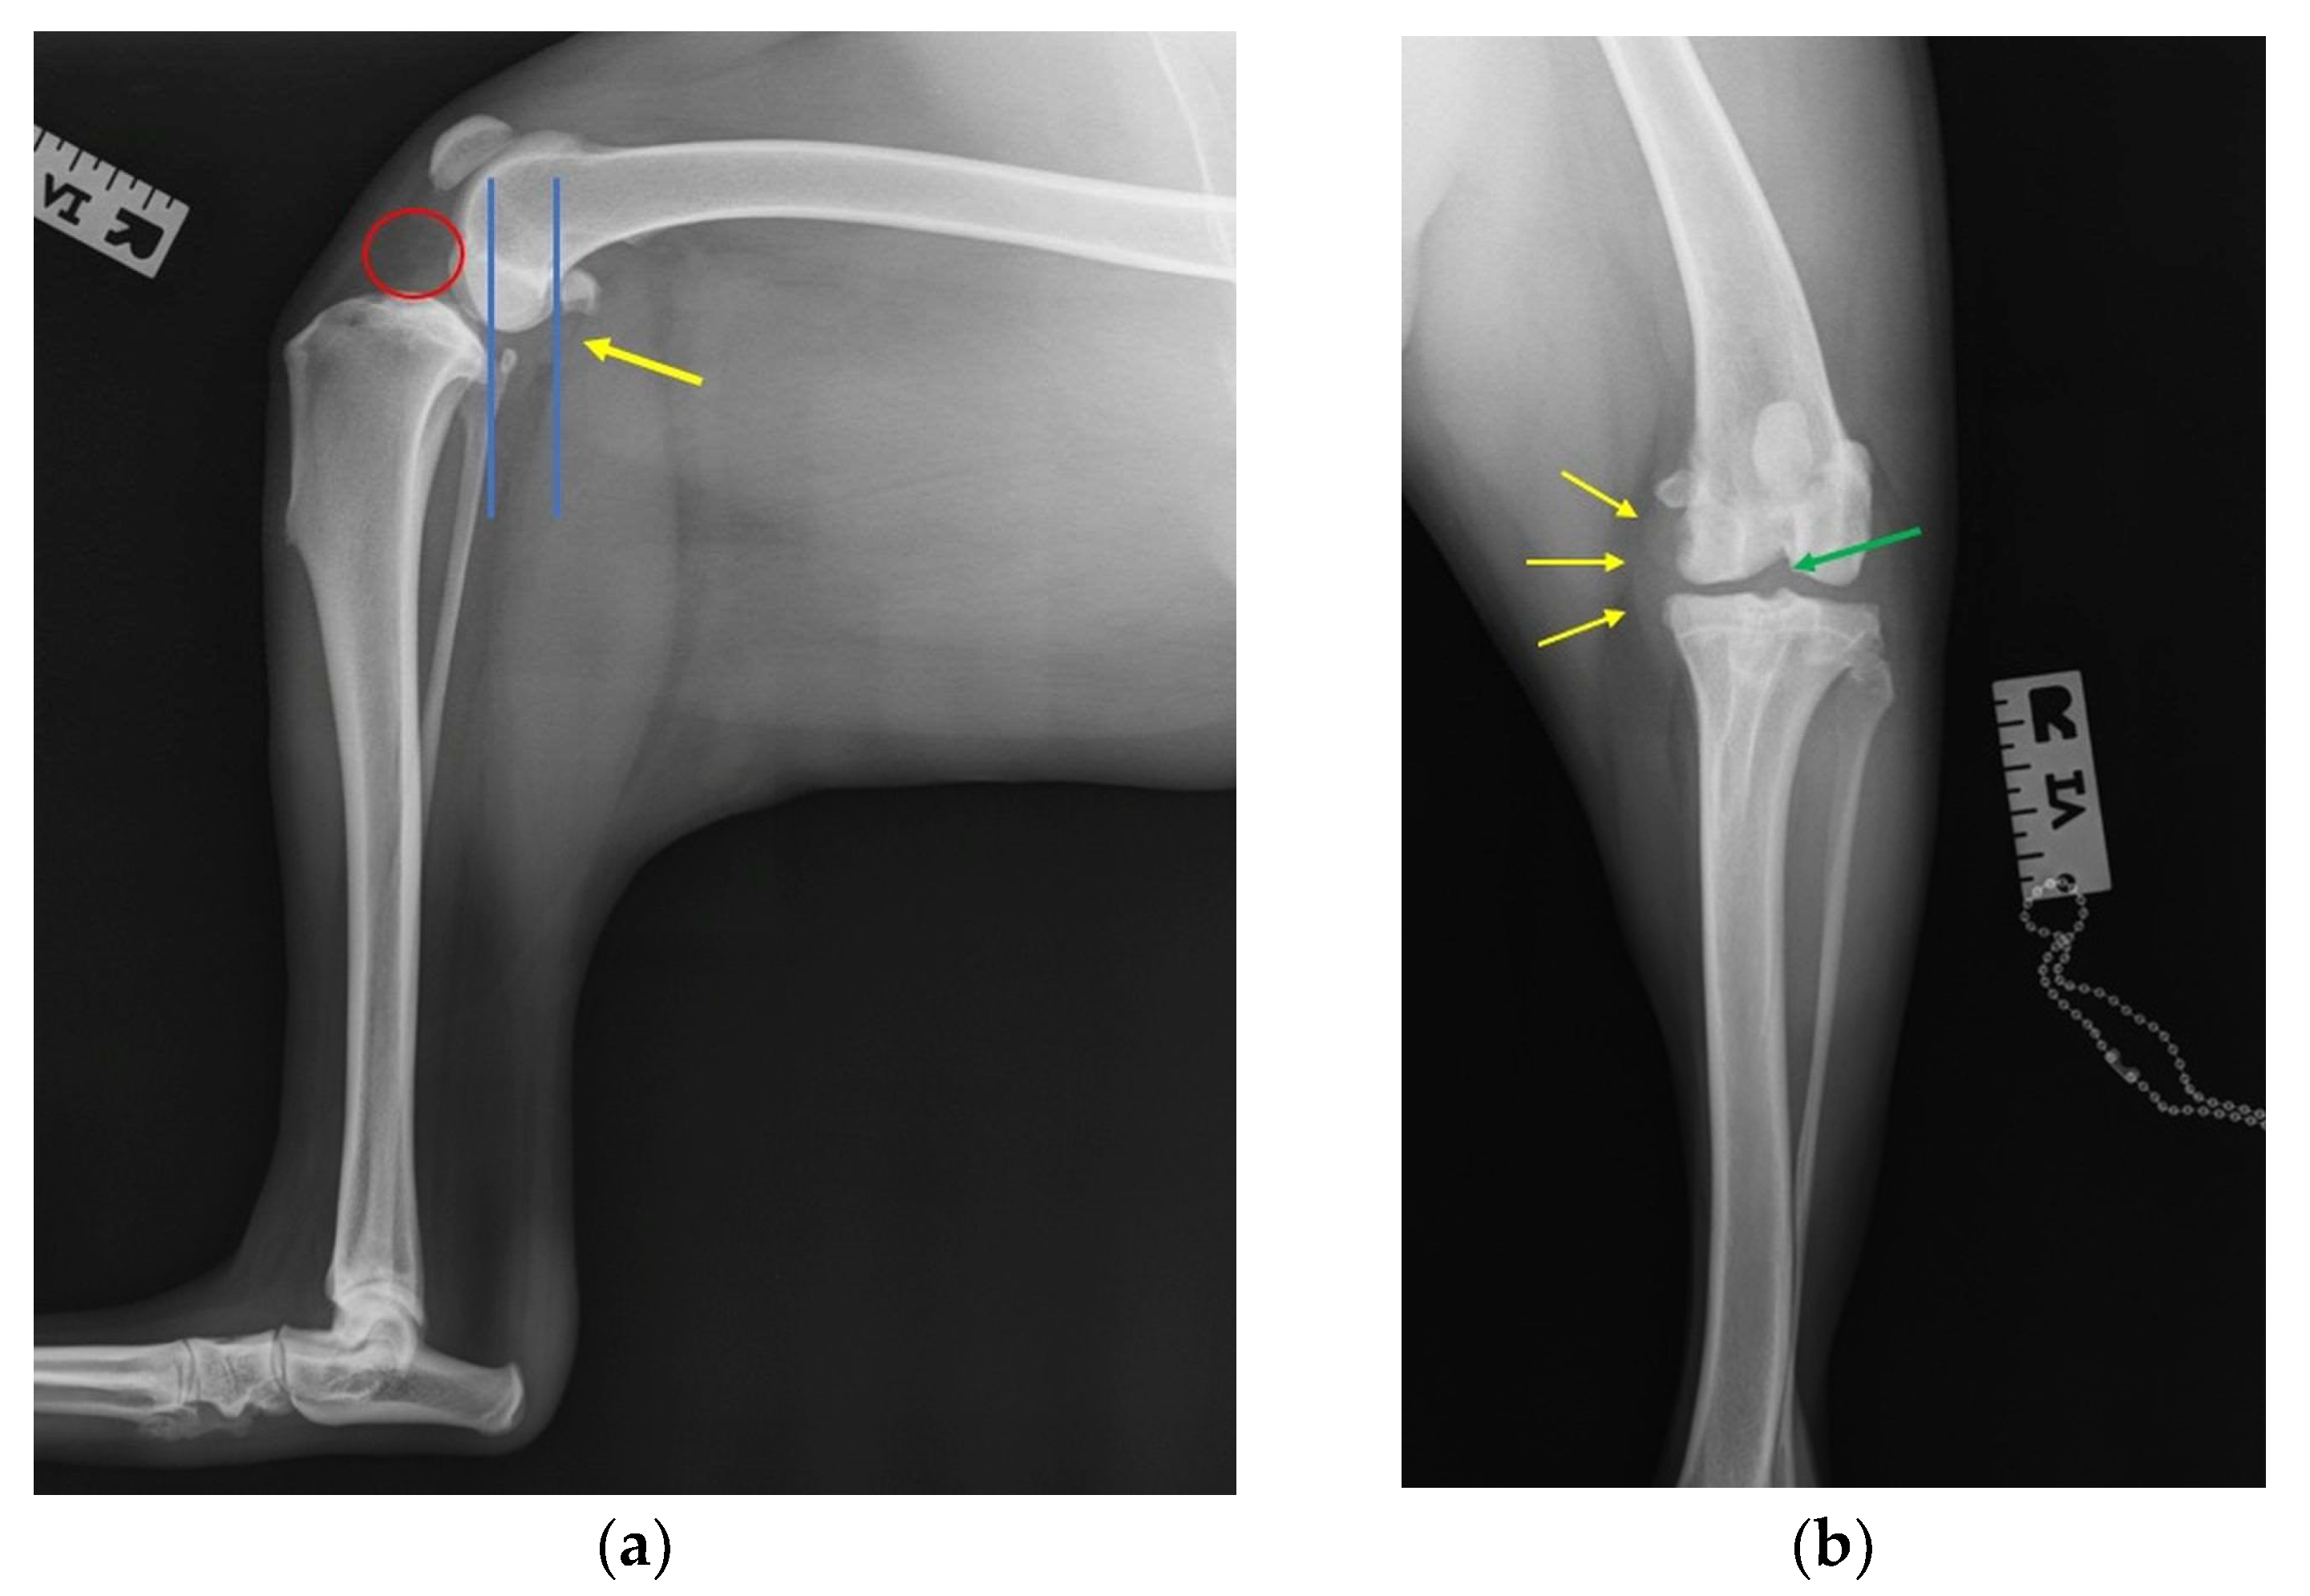

2.3. Radiographic Investigation